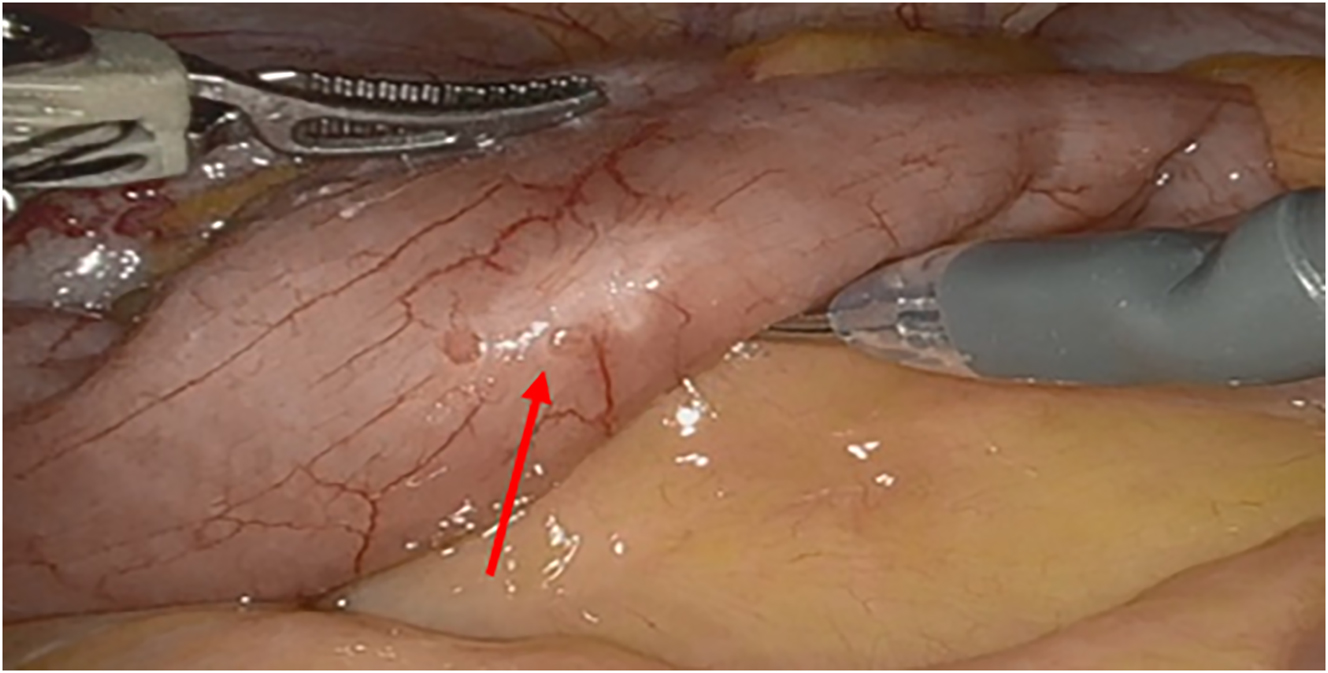

Intestinal endometriosis occurs in 8–12 % of individuals with endometriosis. It is the presence of endometriotic glands and stroma infiltrating at least the muscularis propria of the intestinal wall, as seen in Figure 3. The most common sites are the rectum, sigmoid, and ileocecal junction [37]. The small and large bowel are routinely and systematically evaluated laparoscopically for endometriosis lesions. Currently, there is no data on medical management targeting specifically bowel endometriosis. Bowel endometriosis can be managed surgically with rectal shaving, discoid excision, or segmental resection. Rectal shaving involves shaving the lesion off the affected muscularis layer of the bowel and repairing it with a suture. Discoid excision can be performed through the removal of endometriosis lesions from the bowel lumen followed by closure with a suture or the use of transanal end-to-end anastomosis (EEA) stapler. Referral to colorectal/general surgery for segmental resection should be considered if lesions are multifocal, greater than 3 cm in size, cause significant rectosigmoid stenosis, infiltrate the rectal mucosa, or involve more than 50% of the intestinal circumference [38]. There are many advantages of rectal shaving over discoid excision or segmental resection including a lower risk of complications such as rectovaginal fistula, anastomotic leak, postoperative bleeding, bowel stenosis, and pelvic abscess [38], 39]. When counseling the patient, the risk of recurrence with rectal shaving must be weighed with both short-term complications and long-term postoperative bladder and bowel dysfunction [40] with segmental resection.

Figure 3:

An intraoperative image of the small intestines, with the red arrow pointing to a superficial endometriosis lesion.